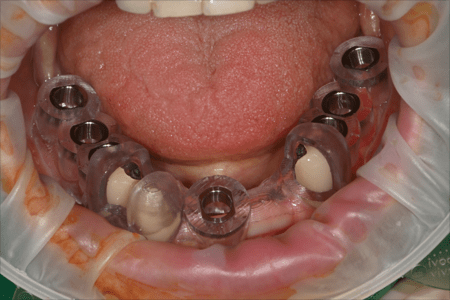

디지털 수술장치

(가이드)

제작

디지털수술장치

가이드 수술